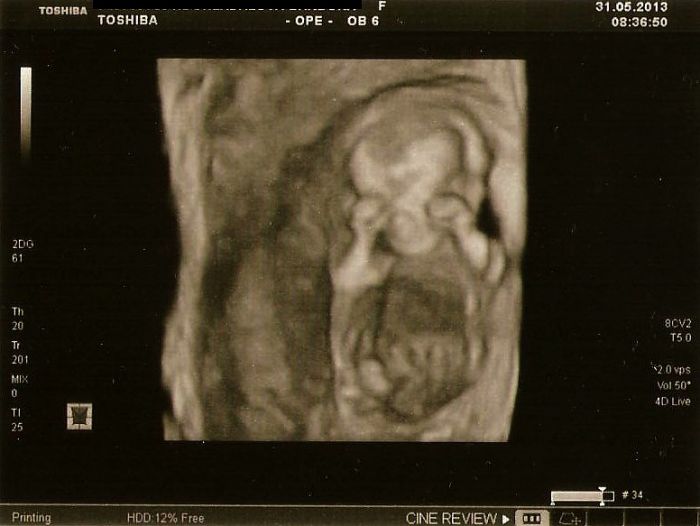

Nakonec k mému překvapení přepla na 3D(4D) a mrňous se chvilku schovával za ručičky a pak zase mával, překvapilo mě, že to už takhle brzo bylo poměrně hezky vidět a nakonec jsme dostali 4 fotečky úplně zadarmo k ceně screeningu a z toho tři 3D..Byl to vážně úžasný zážitek a za ty peníze to určitě stálo

Na té 3D si úspěšně schovává obličejík ručičkama, stydlínek náš malinkej